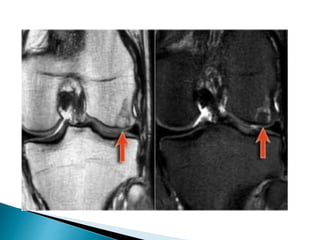

 Typical presentation:well-defined osteolytic lesion in tarsal bone, patella or epiphysis of a long bone in a 20-year old with pain and swelling in a joint.  Abundant edema is almost always present.  DD: Ganglion cyst, osteomyelitis, GCT, ABC, enchondroma.

 Here alesion located in the epi- and metaphysis of the proximal humerus.  The lesion is predominantly calcified.  Coronal T1W image shows lobulated margins due to the calcifications.